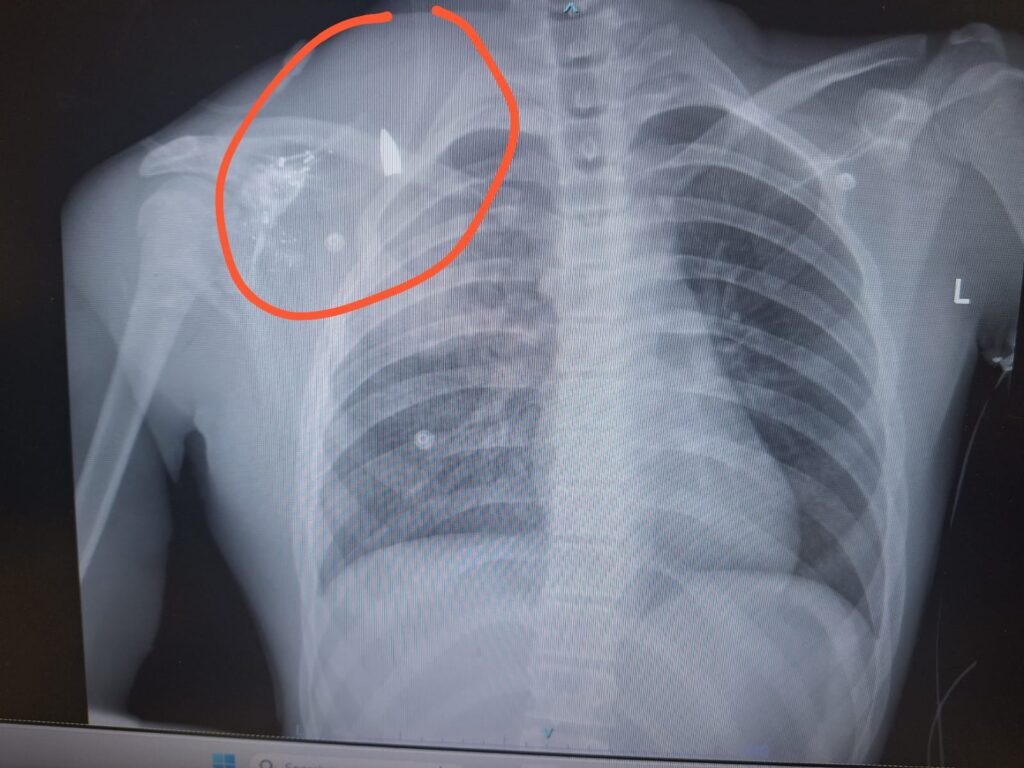

למרות העובדה כי ישנו נער כבן 14 פצוע קשות מירי החיילים, נמנע דובר צה"ל לאורך כל השבת מלציין את העובדה הזאת בכל ההודעות והתדרוכים שהוציא. הערב, ארגון חוננו מפרסם צילום רנטגן המוכיח – כי הנער בן ה-14 נפגע מירי קליע.

הנער נפגע מירי בזרועו, הקליע נכנס בזרוע ונעצר בגבו. הוא סובל מריסוק עצמות בכתף ובזרוע, מפגיעת הדף בריאות ומפגיעות רסיסים. מחר הוא צפוי להיכנס לניתוח. שמו לתפילה – אסיף הלל בן אפרת.